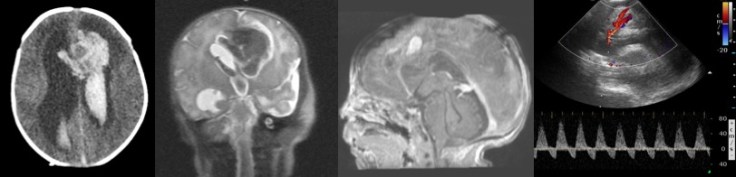

nouveau-né, infection à staphylocoque doré ; hémorragie cérébrale révélatrice d’un anévrisme mycotique - anévrysmes traumatiques : en général en regard du point d’impact